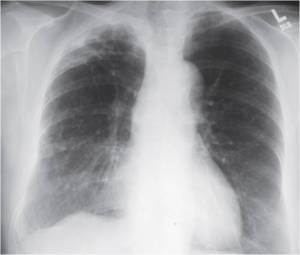

The following are examples of how Active TB may look on CXR:

Primary TB – LLL Infiltrate.

Mimics any pneumonia; occurs in debilitated pts, when Mtb first enters lung, and innate immune system unable to contain it.